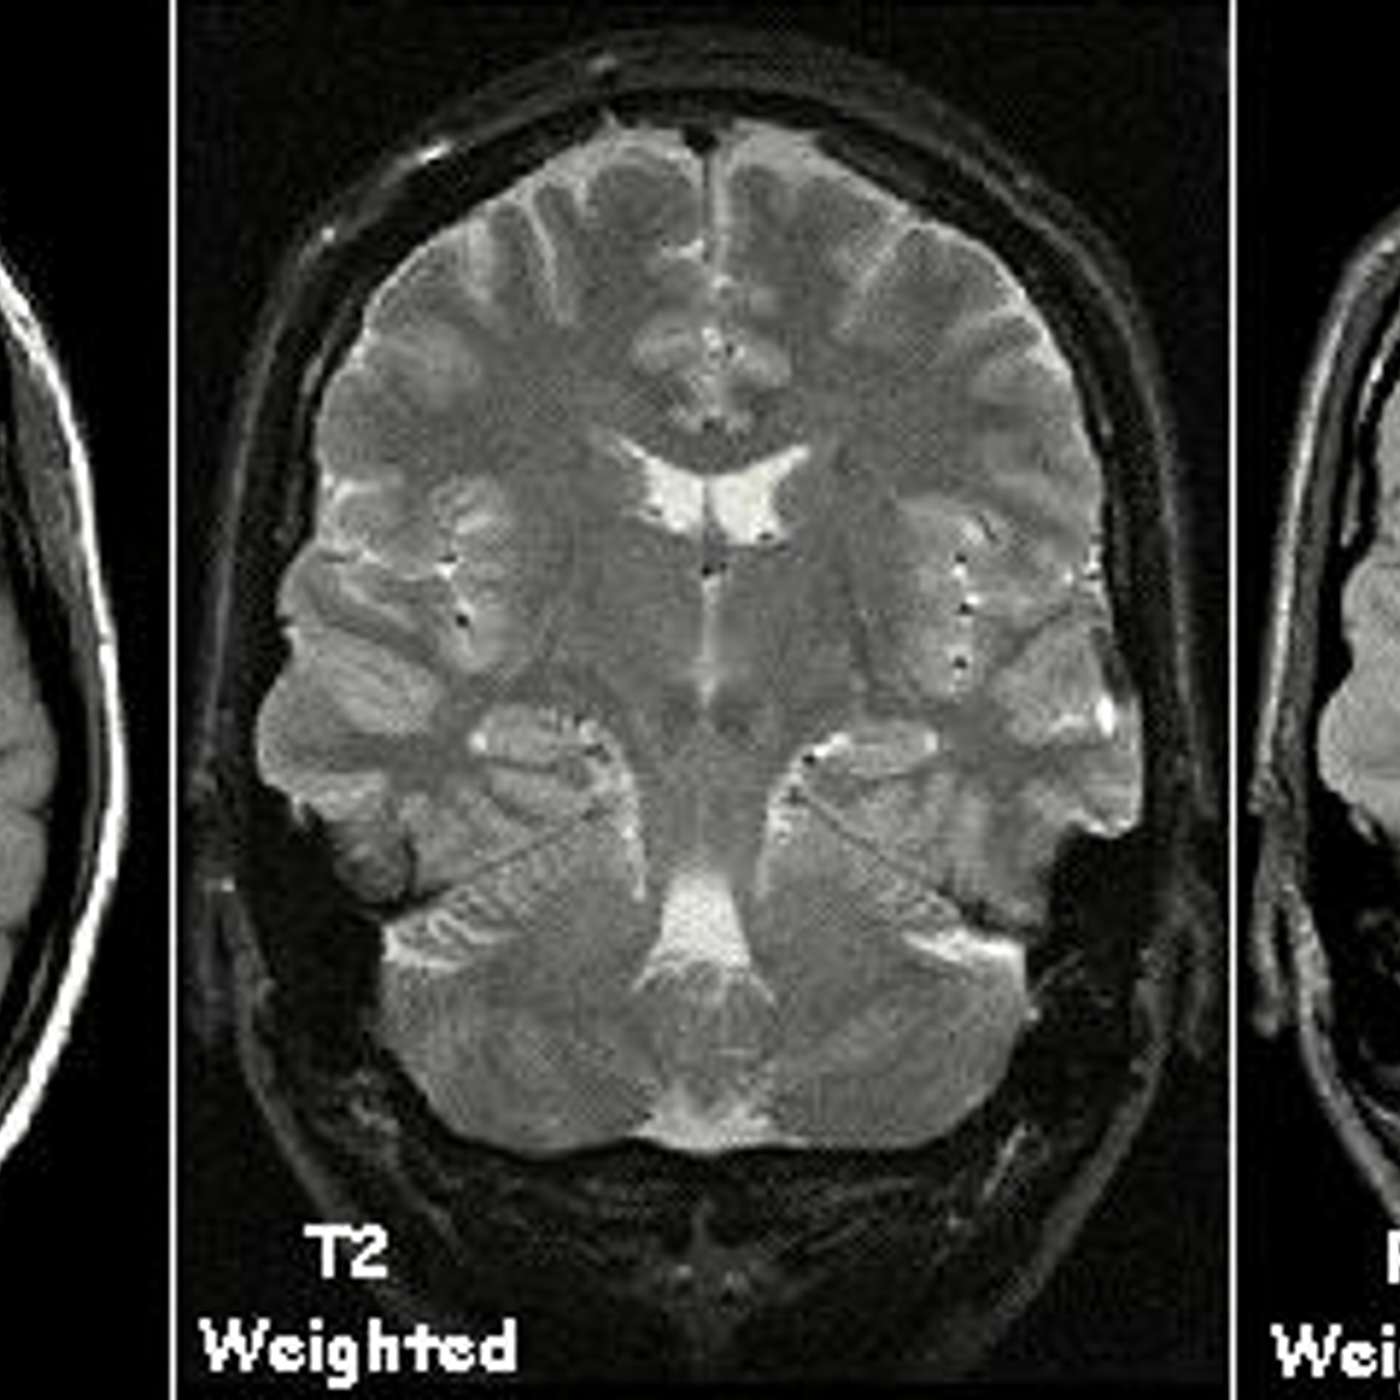

When a programmer hears about processing medical data, they might think it's something serious, something that only universities and research institutes can handle (at least, that's what I thought). As you can see, we're talking about simple grayscale images, which are very easy to process and ideal for things like neural network processing.